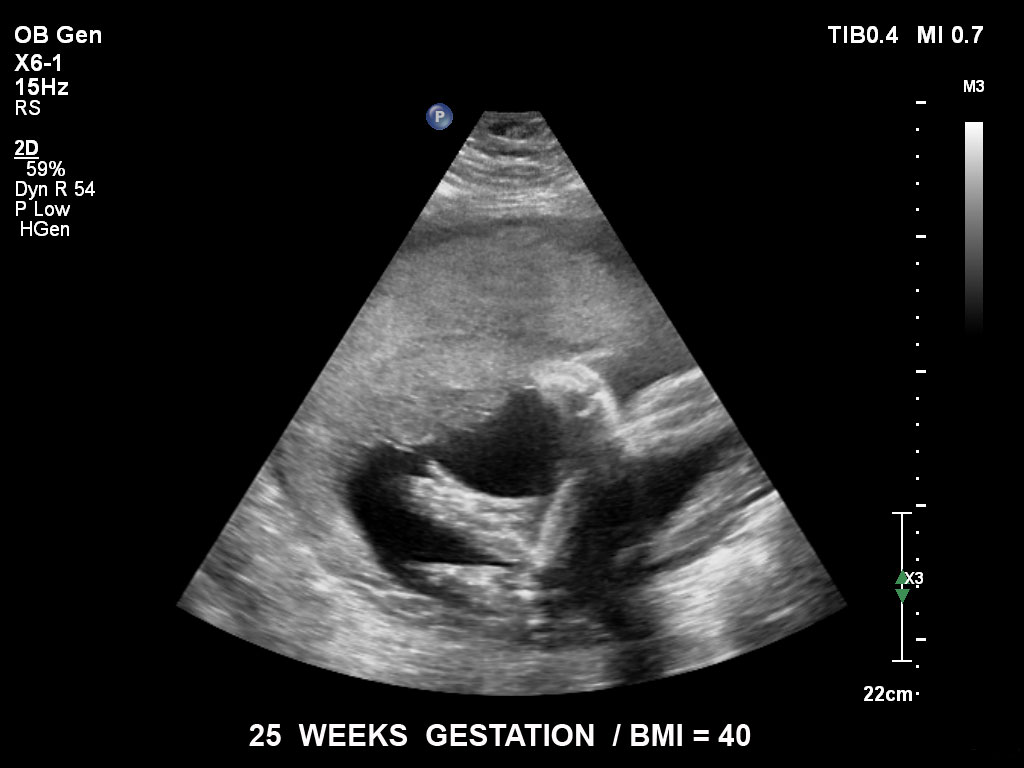

• C5-1 PureWave-Breitband-Convex-Schallkopf für hohe Eindringtiefen in der Gynäkologie und der Geburtshilfe, für Patientinnen mit Schwangerschaftsdiabetes oder vorzeitigem Blasensprung